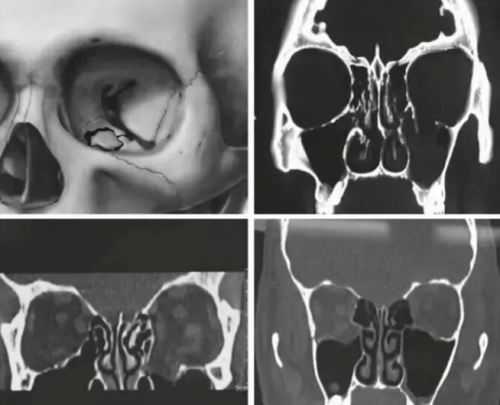

Defnyddio Aloion Titaniwm mewn Atgyweirio Toriadau Orbitol: Cyfleoedd a Heriau